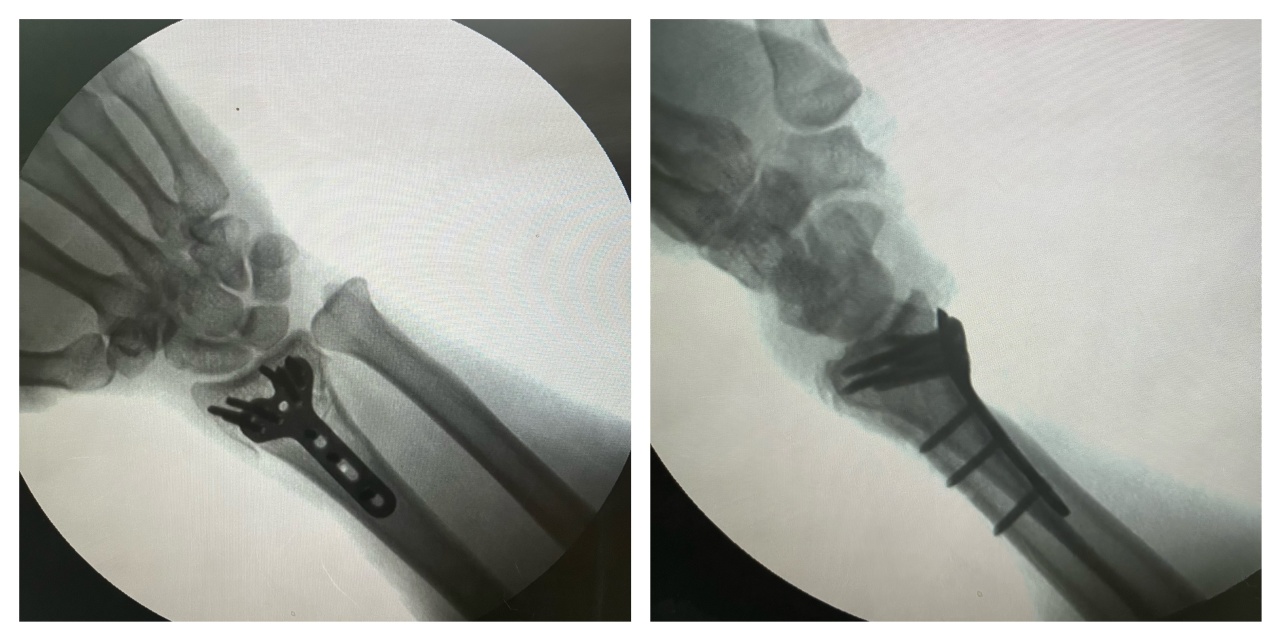

完善术前各项检查后,当晚医院便为患者在插管全麻下实施了“左桡骨远端粉碎性骨折切开复位内固定术”。在黄院长的精准操作和医疗团队的默契配合下,手术全程顺利,成功为患者复位骨折部位并进行牢固固定。

患者术后检查